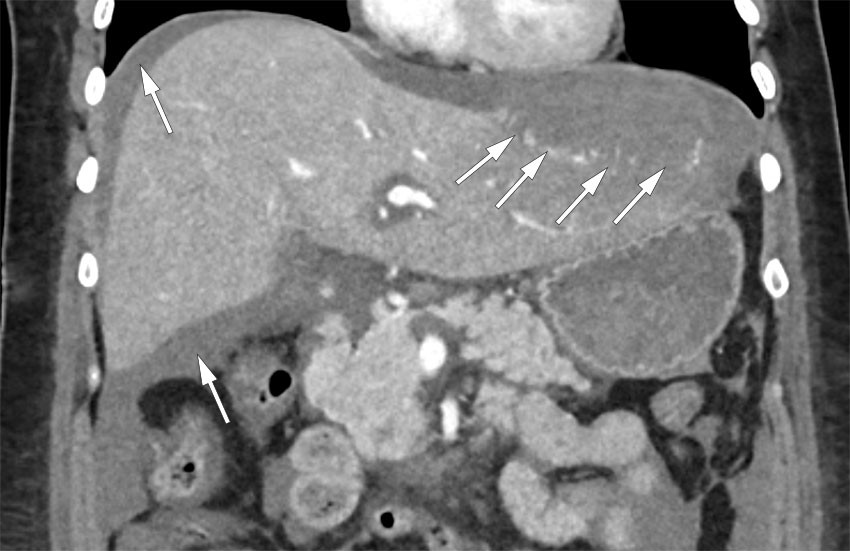

CT-bildet av abdomen viser en spontan leverruptur hos en pasient med HELLP-syndrom, som karakteriseres av massiv hemolyse, forhøyede leverenzymer og blodplatemangel (1). Bildet viser en koronal reformatering av abdomen i portovenøs kontrastfase med kontrastoppladning i intakt leverparenkym, hvor rikelig gjenværende kontrast i det arterielle kretsløpet kan forklares av reduksjon av hjertets minuttvolum som følge av lavt blodvolum og lavt blodtrykk.

CT-undersøkelse av abdomen (arteriell og portovenøs kontrastfase) viste et 8 × 14 cm stort lavattenuerende område fortil i venstre leverlapp og en væskebrem med høy attenuasjon rundt leveren, tolket som spontan leverruptur og leverblødning med subkapsulært hematom. Små høyattenuerende områder i leverparenkymet i arteriell kontrastfase, som ble større i den portovenøse fasen, ble tolket som tegn på ekstravasering av kontrastmiddel og pågående leverblødning.